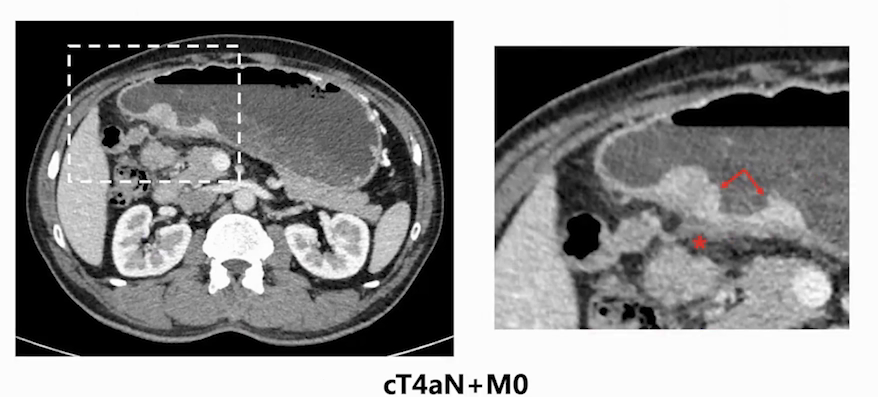

通过腹部增强CT检查,可见肿瘤位于胃窦部,呈溃疡型,周边胃壁浆膜层形态不规则,似累及胃壁浆膜层,同时胃周有可疑肿大淋巴结,判断临床分期可能为CT4aN+M0。